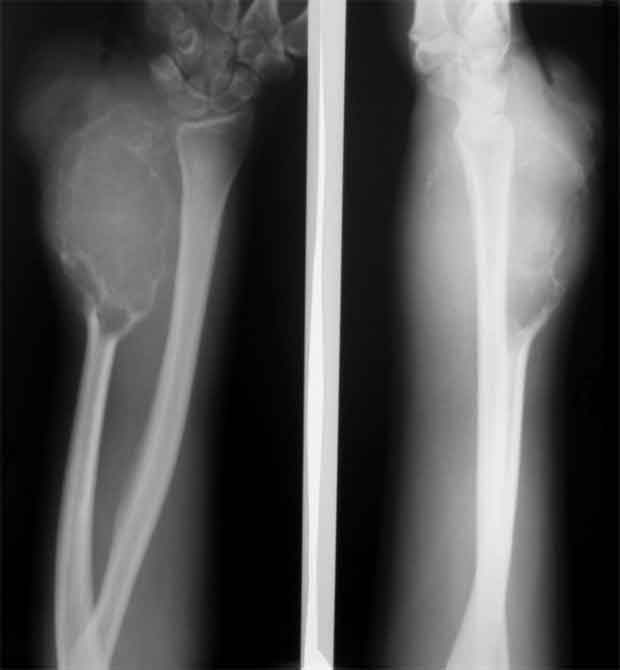

остеобластеокластома локтевой кости

Обратилась пациентка 21 года с опухолью в области н/3 диафиза локтевой кости.

Первые жалобы появились около года назад. Снимков старых под рукой сейчас нет, но опухоль быстро прогрессировала, за полгода увеличилась в размерах более чем в 2 раза. Выполнено несколько гистологических исследований - стеобластеокластома без признаков озлокачествления. После заключительной биопсии на локтевой поврехности предплечья есть рана 5/7 см,не заживет на протяжении 2 мес (натяжение кожи над опухолью), гранулирует, небольшое количество налетов. Планируется резекция, продленная фиксация в гипсе/аппарате - 3-4 мес для формирования контрактуры, уменьшения риска локтевой девиации кисти.

Наличие периостального козырька у основания свидетельствует об вторичном озлокачествлении гигантоклеточной опухоли. Отделяемое неоднократно исследуют цитологически на наличие опухолевых клеток, а также с посевом на микрофлору и чувствительность к а/биотикам. Абластичная резекция в пределах здоровых тканей с замещением дефекта цементном спейсером с антибиотиками в условиях инфекции является адекватным способом лечения.

Привет, Максим! рентгенологически явные признаки малигнизации ГКО.

Уважаемые коллеги, госпитализировали, наконец, эту пациентку, чему не очень рады, как клиническая, так и рентгенологическая картины изменились, кроме того Hb 76.Направил на повторную консультацию к онкологу. Остеобластеокластома может себя так вести?

Клинико-рентгенологически очень похоже на хондросаркому..... Хотя, конечно же, необходимо гистологическое заключение...

Плоховато она выглядит на снимках.

Уважаемые коллеги. По данным рентгенограммы опухоль больше похожа на злокачественную фиброзную гистиоцитому или телеангиоэктотический вариант остеогенной саркомы с поражением кожных покровов. По данным 6 отделения ЦИТО (Бурдыгин В.Н., А.В. Балберкин) и докторской диссертации А.Н. Махсона при поражении низкодифференцированной, т.е. высокозлокачественной опухолью кожных покровов или магистральных сосудисто-нервных структур органосохраняющие оперативные методы лечения не показаны, т.к. имеются отдаленные не диагностируемые метастазы. Показано комбинированное оперативное лечение по принципам неоадъювантной ПХТ.

Может при озлокачествлении (литическая форма), но уж больно похоже на хондро SA.